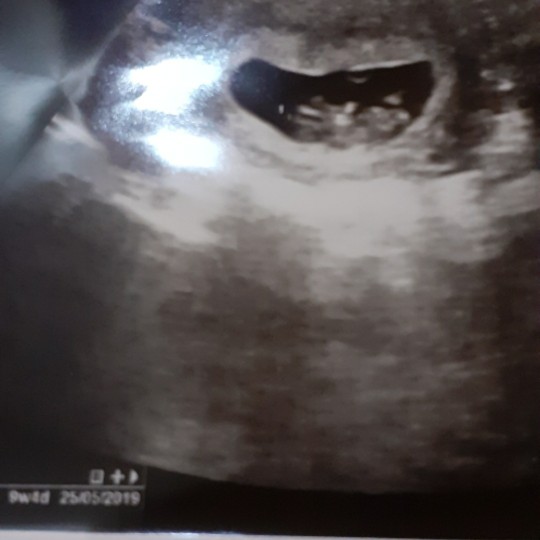

9 week aja boleh yah